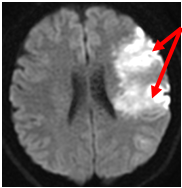

【心原性脳塞栓症】

最も重症なタイプが脳塞栓です。主に心臓の中で出来た血の塊(血栓)が血流に乗って運ばれ、脳の太い血管を詰めてしまうため急に重篤な片麻痺や意識障害、言語障害が出現するものです。心臓の中に血栓が出来る原因としては不整脈の一種の心房細動というものが重要です。アテローム血栓性脳梗塞と違い、いきなり血管がつまるため症状は突然に起こり、また太い脳血管がつまることが多いので症状も重い場合が多いと言えます。

Apoplexy 6

【MRI】

MRA

【MRA】

翌日のCT

【翌日のCT】

心房細動からの塞栓にて右内頸動脈が閉塞史、広範囲脳梗塞を呈している。翌日には脳が強く腫れてきている。